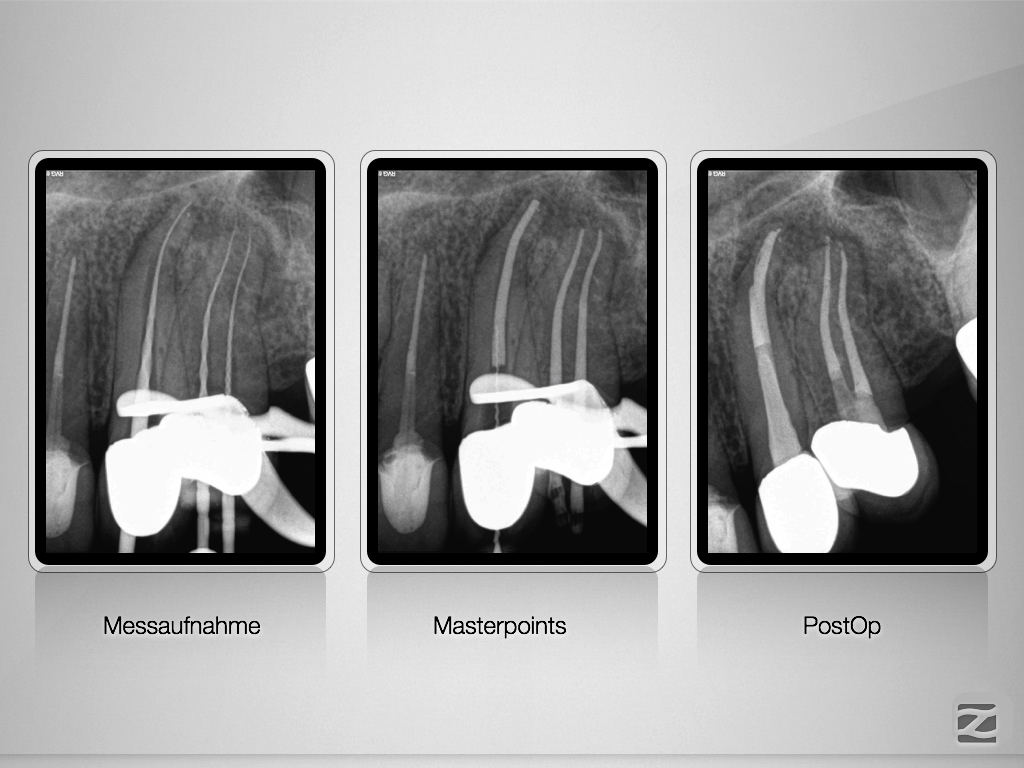

23 & 24 D.003

Ursache und Wirkung